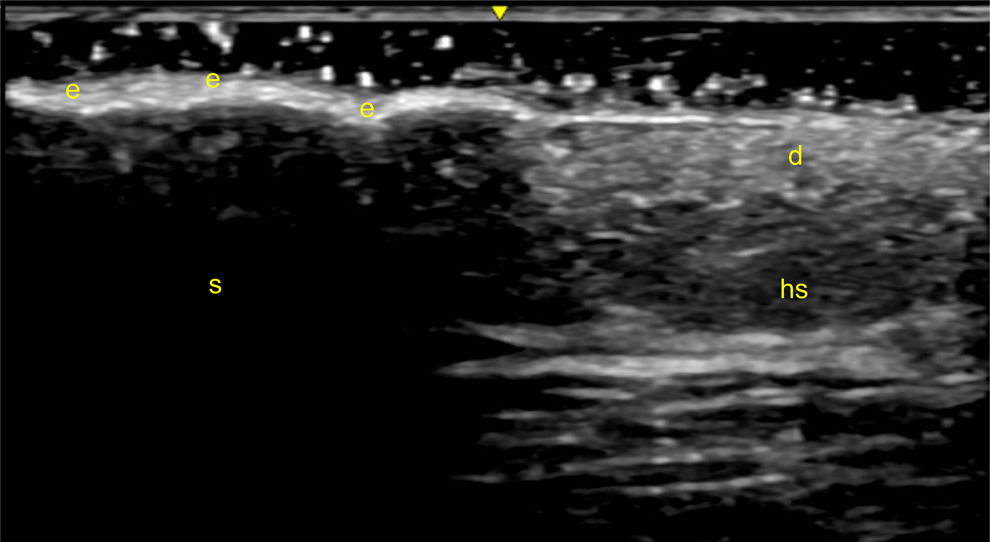

Sonographic Evaluation of Skin in Psoriatic Arthritis: High-resolution ultrasound with very high-frequency probes allows for a detailed evaluation of the skin morpho-structural features [120,121]. Ultrasound effectively identifies several abnormalities in psoriatic plaques, differentiating affected from healthy skin [122,123]. Changes include increased skin thickness and reduced echogenicity compared to unaffected areas [123,124]. Thickening is due to inflammation, edema, and hypervascularization of the papillary dermis, often accompanied by keratinocyte proliferation and desquamation [7,125]. Additionally, edema-related restructuring of the dermis increases collagen fiber density, reducing skin firmness [126].

In psoriatic skin both the epidermis and dermis appear thickened [127], and dermis echogenicity is reduced [128]. Although increased blood flow is often seen, the subcutaneous tissue usually remains unchanged [126].

Psoriatic plaques exhibit a range of ultrasound characteristics, most notably a significant thickening of both the epidermis and dermis, often accompanied by increased vascularity in the dermis, as revealed by PD. In certain cases, the degree of epidermal thickening is so substantial that it creates an acoustic shadow impairing the visualization of deeper structures (Fig. 4) [20].

Fig. 4.Psoriatic plaque. Sonographic image obtained using Logiq e US system with an 8–18i MHz linear transducer. Comparative image of the edge of a psoriatic plaque, distinguishing healthy skin (hs) from the plaque itself. Note the thickening of the epidermis (e), which generates an acoustic shadow (s), hindering the visualization of deeper structures. d=dermis.

Though typical of psoriatic skin, these sonographic features may overlap with other dermatological conditions, such as contact dermatitis, atopic eczema, or acanthomas [127]. It is also important to account for variations in skin thickness due to factors like gender, sun exposure, and body region, requiring comparisons between lesional and non-lesional skin in the same anatomical area [126]. Ultrasound allows monitoring of treatment response, demonstrated by a reduction in epidermal and dermal thickness and the resolution of the superficial hypoechoic band [129,130].